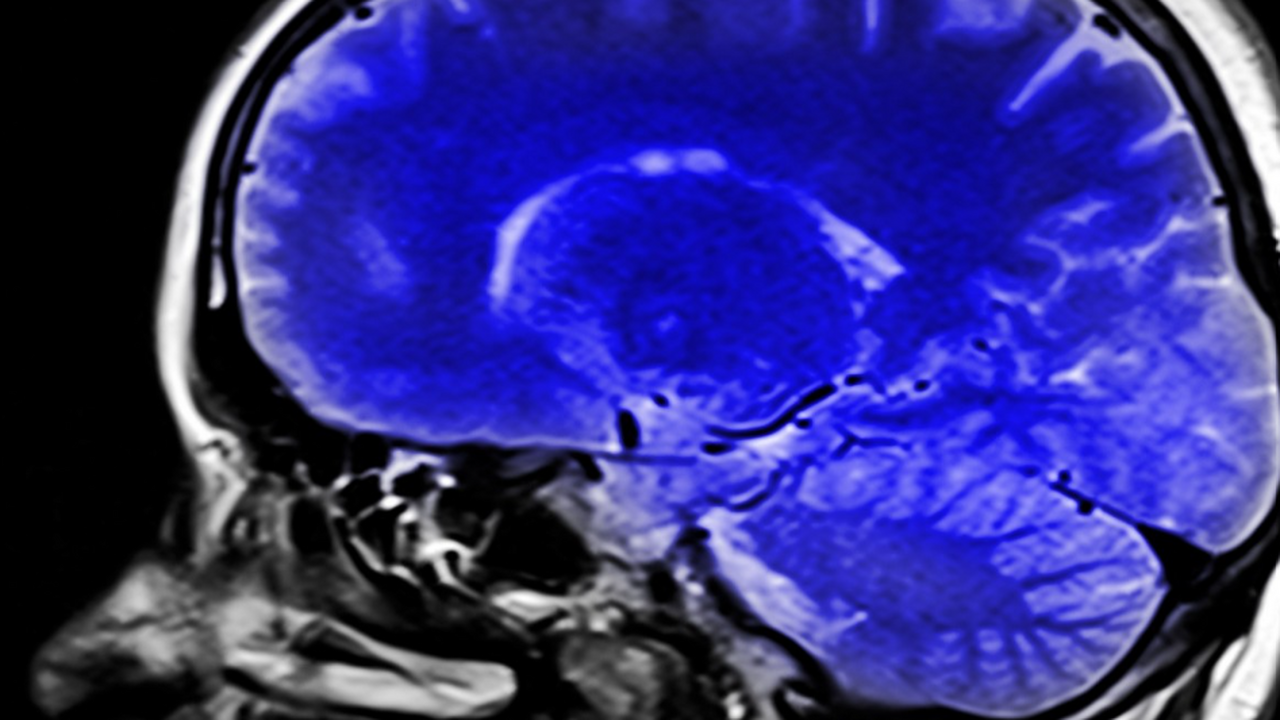

Как выяснилось, наибольшую тревогу вызывают не подкожные жировые отложения, а жир, накапливающийся глубоко в органах. При детальном сканировании тела и мозга с помощью магнитно-резонансной томографии наиболее выраженные неблагоприятные изменения фиксировались именно при так называемом эктопическом ожирении.

Исследователи установили, что оба этих профиля тесно связаны с уменьшением объёма серого вещества мозга, отвечающего за обработку информации, а также с увеличением очагов гиперинтенсивности белого вещества — маркеров повреждения мелких сосудов. Эти изменения совпадали с признаками ускоренного старения мозга и сопровождались снижением когнитивных показателей.